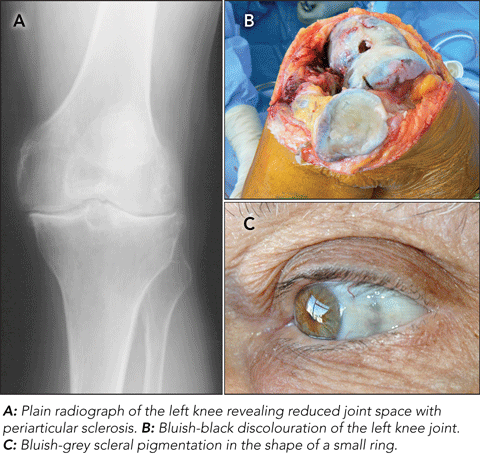

A 77-year-old man with no significant medical history presented to the orthopaedic clinic of a metropolitan hospital with longstanding left mechanical knee pain. Examination and x-ray revealed features consistent with degenerative arthritis (Figure, A), and he subsequently underwent total knee arthroplasty. During surgery, a bluish-black pigmentation of the bone and the cartilage of the knee joint was noted (Figure, B). The patient’s surgery and recovery were uneventful. It was later discovered that he had a previously undiagnosed rare metabolic disorder, alkaptonuria, which affects one in 250 000 to 1 000 000 people worldwide.1

Alkaptonuria was one of the first inborn errors of metabolism to be described, in 1908.2 It is caused by mutations in the homogentisate 1,2-dioxygenase (HGD) gene, which results in a deficiency of HGD, which catabolises homogentisic acid (HGA). This leads to accumulation and deposition of HGA in cartilaginous tissues, causing a bluish-black discolouration (ochronosis).3 Ochronosis is generally asymptomatic, but ochronotic arthropathy due to deposition of pigments in the joints is common.3